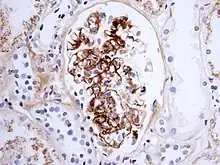

Immune Complex Glomerulonephritis, as seen in Henoch-Schönlein purpura; this is an example of IgA involvement in a nephropathy

The reaction can take hours, days, or even weeks to develop, depending on whether or not there is immunological memory of the precipitating antigen. Typically, clinical features emerge a week following initial antigen challenge, when the deposited immune complexes can precipitate an inflammatory response. Because of the nature of the antibody aggregation, tissues that are associated with blood filtration at considerable osmotic and hydrostatic gradient (e.g. sites of urinary and synovial fluid formation, kidney glomeruli and joint tissues respectively) bear the brunt of the damage. Hence, vasculitis, glomerulonephritis and arthritis are commonly associated conditions as a result of type III hypersensitivity responses.[10]

As observed under methods of histopathology, acute necrotizing vasculitis within the affected tissues is observed concomitant to neutrophilic infiltration, along with notable eosinophilic deposition (fibrinoid necrosis). Often, immunofluorescence microscopy can be used to visualize the immune complexes.[10] Skin response to hypersensitivity of this type is referred to as an Arthus reaction and is characterized by local erythema and some induration. Platelet aggregation, especially in microvasculature, can cause localized clot formation, leading to blotchy hemorrhages. This typifies the response to injection of foreign antigen sufficient to lead to the condition of serum sickness.[11]